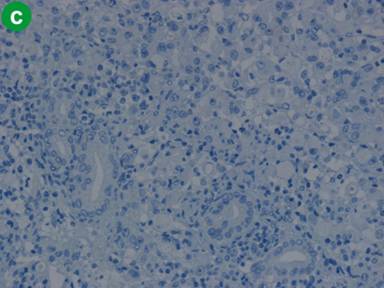

Macroscopically, the tumor measured 1.5x1.5x2 cm and the tumor surface was exposed at the papilla, showing that its surface was nodular, but there was no ulceration. Histologically, signet-ring cell carcinoma was predominant, but partially well- to poorly-differentiated tubular adenocarcinoma also existed in the lesion (Figure 3a). Signet-ring cell carcinoma arose from the ampulla of Vater, slightly involving the muscularis propria of the duodenum and infiltrating the pancreatic parenchyma. The cytoplasm of the signet-ring cell carcinoma was positive for periodic acid Schiff staining (Figure 3b). Lymphatic and vascular involvement was seen in parts, but resected lymph nodes were free from metastasis. Immunohistochemical staining was performed and both the signet-ring cells and the adenocarcinoma cells were positive for human gastric mucin (45M1) (Figure 4). Both types of tumor cells were positive for CK7, MUC1 and MUC6, but negative for CK20, MUC2 and CD10 (Figure 5). The signet-ring cell carcinoma was partially positive for CDX2 (Figure 6). The carcinoma of the ampulla of Vater was diagnosed as T3N0M0 stage IIA according to the International Union Against Cancer TNM classification. The patient did not receive chemotherapy. Six months after surgery, the patient developed pneumonia. Subsequently, the pneumonia worsened and the diabetes mellitus also deteriorated. The patient finally died from multiple organ failure due to sepsis. However, no recurrence of the signet-ring cell carcinoma was detected on repeated imaging studies.

Figure 5. Both signet-ring cells and adenocarcinoma cells stained positively for CK7, but negatively for CD20 (a. H&E, x100; b. Immunohistochemical findings for CK7, x100; c. CK20, x100). |

Kimura et al. histologically subdivided carcinoma of the ampulla of Vater into the intestinal-type and pancreaticobiliary-type [22]. Fischer and Zhou demonstrated differences between these groups on staining for immunohistochemical markers. The intestinal type expressed the immunohistochemical marker profile of intestinal mucosa, that is, negative for CK 7 and positive for CK 20 and MUK2. However, the pancreaticobiliary type shows the immunohistochemical profiles of pancreaticobiliary mucosa, that is, positive for CK 7 and negative for CK 20 and MUC 2 [23]. Fischer and Zhou described the immunohistochemical profiles of three signet-ring cell carcinomas of the ampulla of Vater as follows: all the specimens of signet-ring cell carcinoma were negative for CK 7 and positive for CK 20 and MUC 2 [23]. In our case, the tumor cells were positive for CK7 and negative for CK20 and MUC 2. We suspected that there may be several patterns of immunohistochemical staining for apomucin in signet-ring cell carcinoma of the ampulla of Vater. Our case was thought to be similar to the pancreaticobiliary type because of the positive findings for CK7 and the negative finding for MUC2 staining. But we think it is difficult to conclude that our case was a real pancreaticobiliary type using only these immunohistochemical findings. The positive finding for human gastric mucin (45M1) staining also suggested that both the signet-ring cell carcinoma and the adenocarcinoma in our case were similar to the pancreaticobiliary type. Sonoue et al. suggested that the pancreatobiliary mucosa of the ampulla of Vater demonstrates regenerative hyperplasia in response to some stimuli, representing a functional modification and expressing some features of a gastric surface marker for immunohistochemical staining [24].